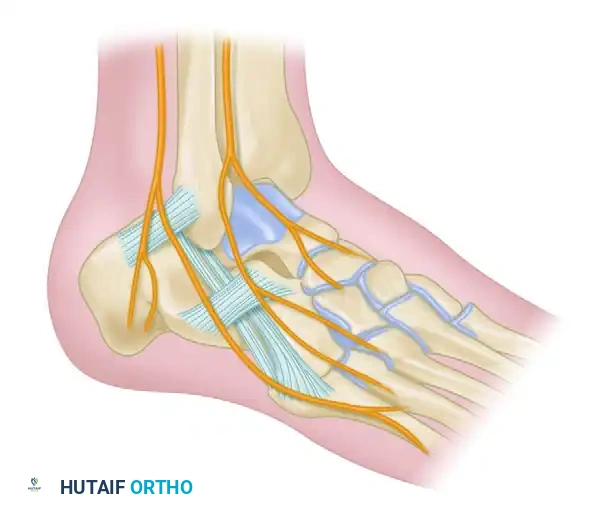

التشريح ومفاصل القدم المستهدفة

لفهم طبيعة الجراحة، يجب أولا التعرف على التشريح المعقد للقدم. الجزء الخلفي من القدم مسؤول عن الحركات الجانبية والتكيف مع الأسطح غير المستوية. تتضمن عملية إيثاق المفاصل الثلاثي دمج المفاصل الثلاثة التالية

مفصل تحت الكاحل

يقع هذا المفصل بين عظمة الكاحل وعظمة العقب. وهو المفصل الرئيسي المسؤول عن حركة القدم للداخل والخارج. تلف هذا المفصل يؤدي إلى ألم شديد عند المشي على أسطح غير مستوية.

المفصل الكاحلي الزورقي

يقع بين عظمة الكاحل والعظمة الزورقية في منتصف القدم. يلعب دورا حيويا في مرونة قوس القدم وتوزيع الوزن أثناء المشي.

المفصل العقبي النردي

يربط بين عظمة العقب والعظمة النردية في الجزء الخارجي من القدم. يساهم في استقرار القدم ودعم حركتها الميكانيكية.

عندما يتم دمج هذه المفاصل الثلاثة معا لتصبح كتلة عظمية واحدة صلبة، يختفي الألم الناتج عن احتكاك العظام المتضررة، وتستعيد القدم استقامتها الطبيعية.

حماية الأعصاب والأوتار

من أهم خطوات الجراحة هي الحماية الدقيقة للأنسجة الحيوية. يقوم الجراح بحماية الأوتار الشظوية والفرع المشترك للعصب الربلي في النهاية الخلفية للشق الجراحي. كما يتم الانتباه للفرع الظهري للعصب الربلي والأعصاب السطحية الأخرى لضمان عدم تضررها أثناء العملية.